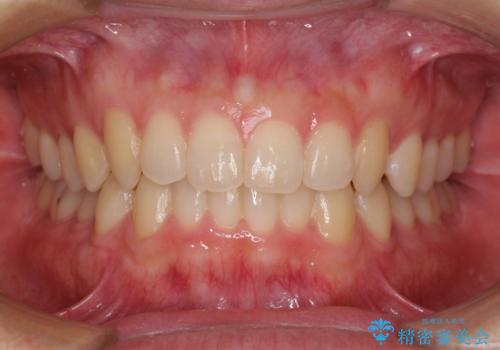

出っ歯 すれ違い咬合の改善

奥歯の倒れた歯を改善 インビザラインでの矯正治療

気になる前歯を整えたい インビザライン・ライトでの矯正治療

担当医 藤巻太一朗

気になる前歯をインビザラインで綺麗に